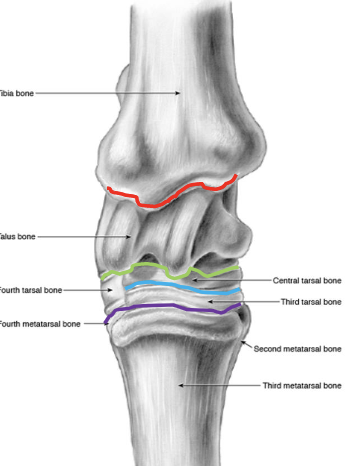

joints of the tarsus

red- tibiotarsal (or tarsocrural)

green- proximal intertarsal

blue- distal intertarsal

purple- tarsometatarsal

which joints of the tarsus communicate w/ e/o

tibiotarsal and proximal intertarsal joints

which tarsal joints are the most common sites of arthritis in horses

distal intertarsal and tarsometatarsal